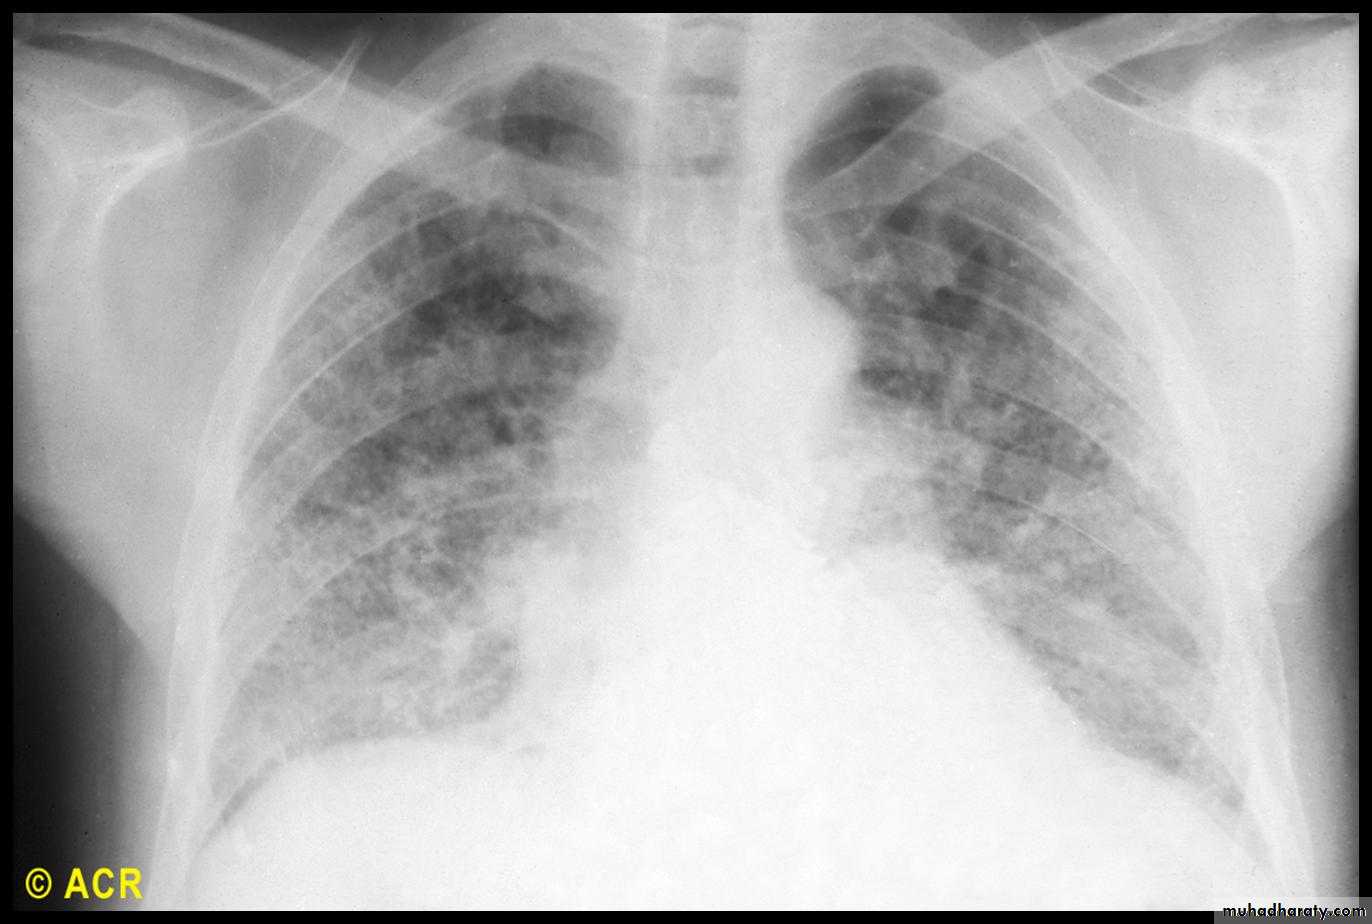

Pulmonary involvement

This is a major cause of morbidity and mortality.Pulmonary hypertension complicates longstanding disease and is six times more prevalent in LCSS than in DCSS.

It presents with rapidly progressive dyspnoea (more rapid than interstitial lung disease), right heart failure and angina, often in association with severe digital ischaemia.

Fibrosing alveolitis mainly affects patients with DCSS who have topoisomerase 1 antibodies.

Others: aspiration pneumonia, bronchiectesis, hidebound chest, alveolar and bronchial carcinoma.

Chest X-ray, transthoracic echocardiography and lung function tests are recommended to assess for interstitial lung disease and pulmonary hypertension.High-resolution lung CT is recommended if interstitial lung disease suspected .If pulmonary hypertension is suspected, right heart catheter measurements should be arranged at a specialist cardiac centre.